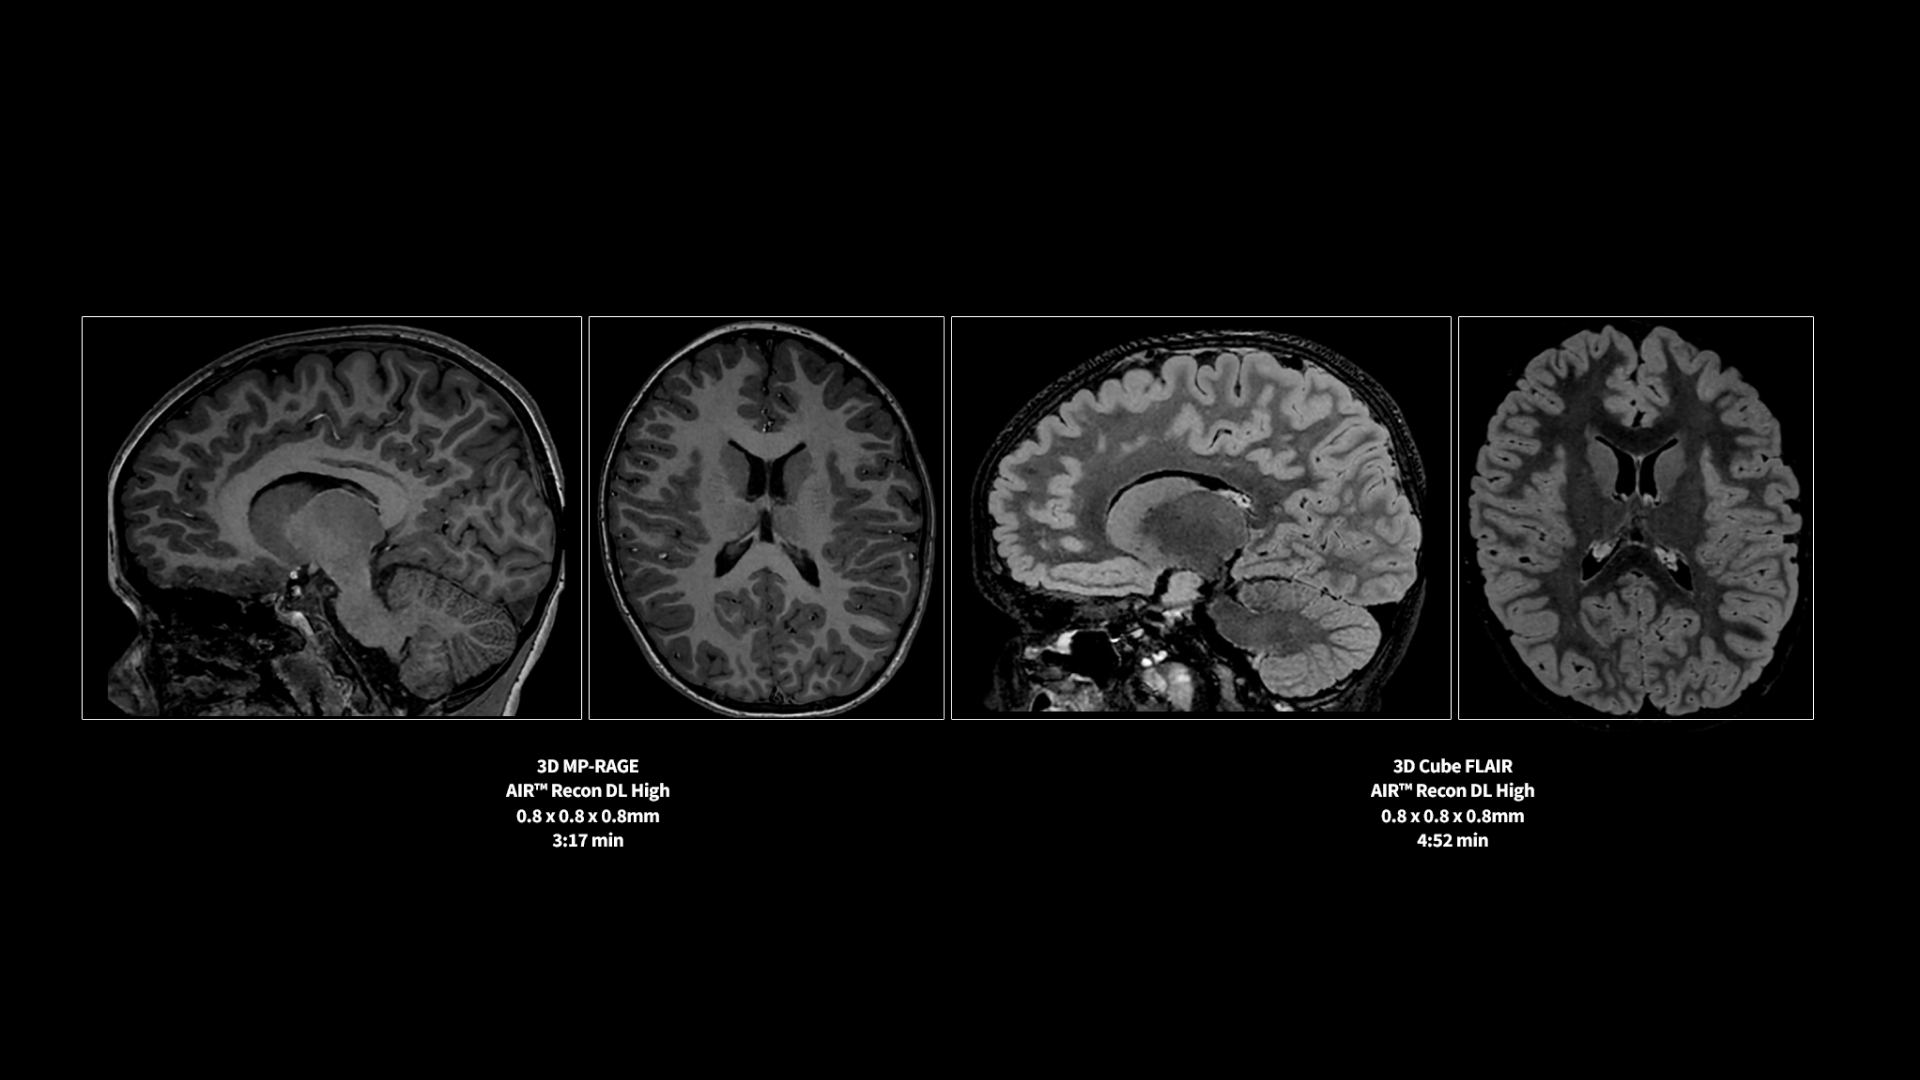

Revolutionary, deep-learning-based reconstruction techniques such as AIR™ Recon DL provide sharper, clearer, and accurate images

Pin-sharp image quality and exceptional speed with AIR Recon DL and Sonic DL​

Experience pin-sharp precision and remarkable speed with a 3T SIGNA Premier MRI scanner, coupled with AIR Recon DL and Sonic DL™.

​With built-in sleep mode to conserve energy and the ability to reduce power consumption through reduced scan time of up to 50% with AIR Recon DL, SIGNA Premier is a sustainable investment you can feel good about.